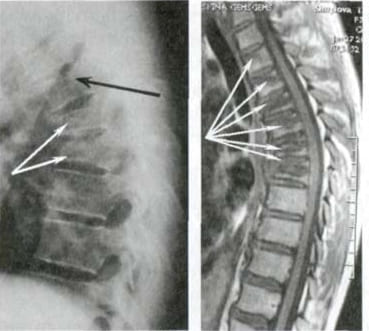

Mire esta radiografía. Es la columna de una persona de 44 años, pero parece la de un anciano. Antes, este tipo de daño aparecía después de los 60 años y, hoy, es muy común en personas de poco más de 40. Estos cambios progresan con la edad, y ignorarlos amenaza con una pérdida completa de movilidad.

Columna de un paciente de 44 años: todo comenzó con un dolor simple, pero en una semana apareció la hernia, y en dos semanas — desplazamiento de las vértebras, compresión de nervios y silla de ruedas.

Mire estas fotografías. Esto es lo que les sucedió a todos los que ignoraron los síntomas. Hoy, estas personas están completamente sin esperanza, y muchos de ellos no tienen a quién acudir en busca de ayuda. ¿Realmente, quiere un destino así?

"Joroba de viuda" — deformación de las vértebras y dolor crónico, insoportable, que se intensifica cada día.

Hernia de disco intervertebral, compresión de los nervios, pérdida de sensibilidad y parálisis parcial de las piernas.